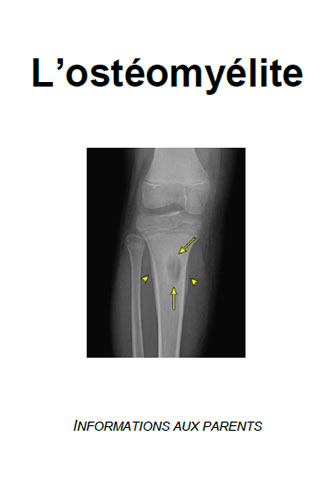

• L’ostéomyélite